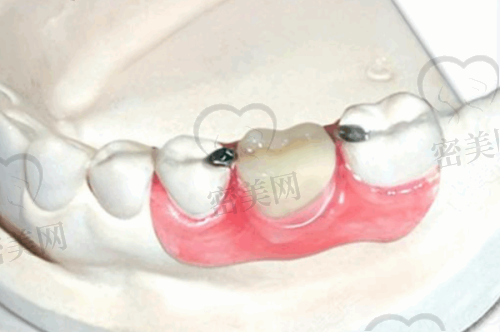

在种植牙领域,医生也有一定的技术优势,包括单颗牙和多颗牙种植。门诊部提供预约服务,方便患者合理安排时间。患者在进行种植牙手术时,无论是单颗牙缺失还是多颗牙缺失,都能在这里得到相应的治疗。

除了牙齿矫正和种植牙这两个特色项目外,慈溪牙牙乐口腔门诊部还开展牙齿拔除等项目。这满足了不同患者的多种口腔需求,患者不用为了不同的口腔问题而奔波于不同的机构。